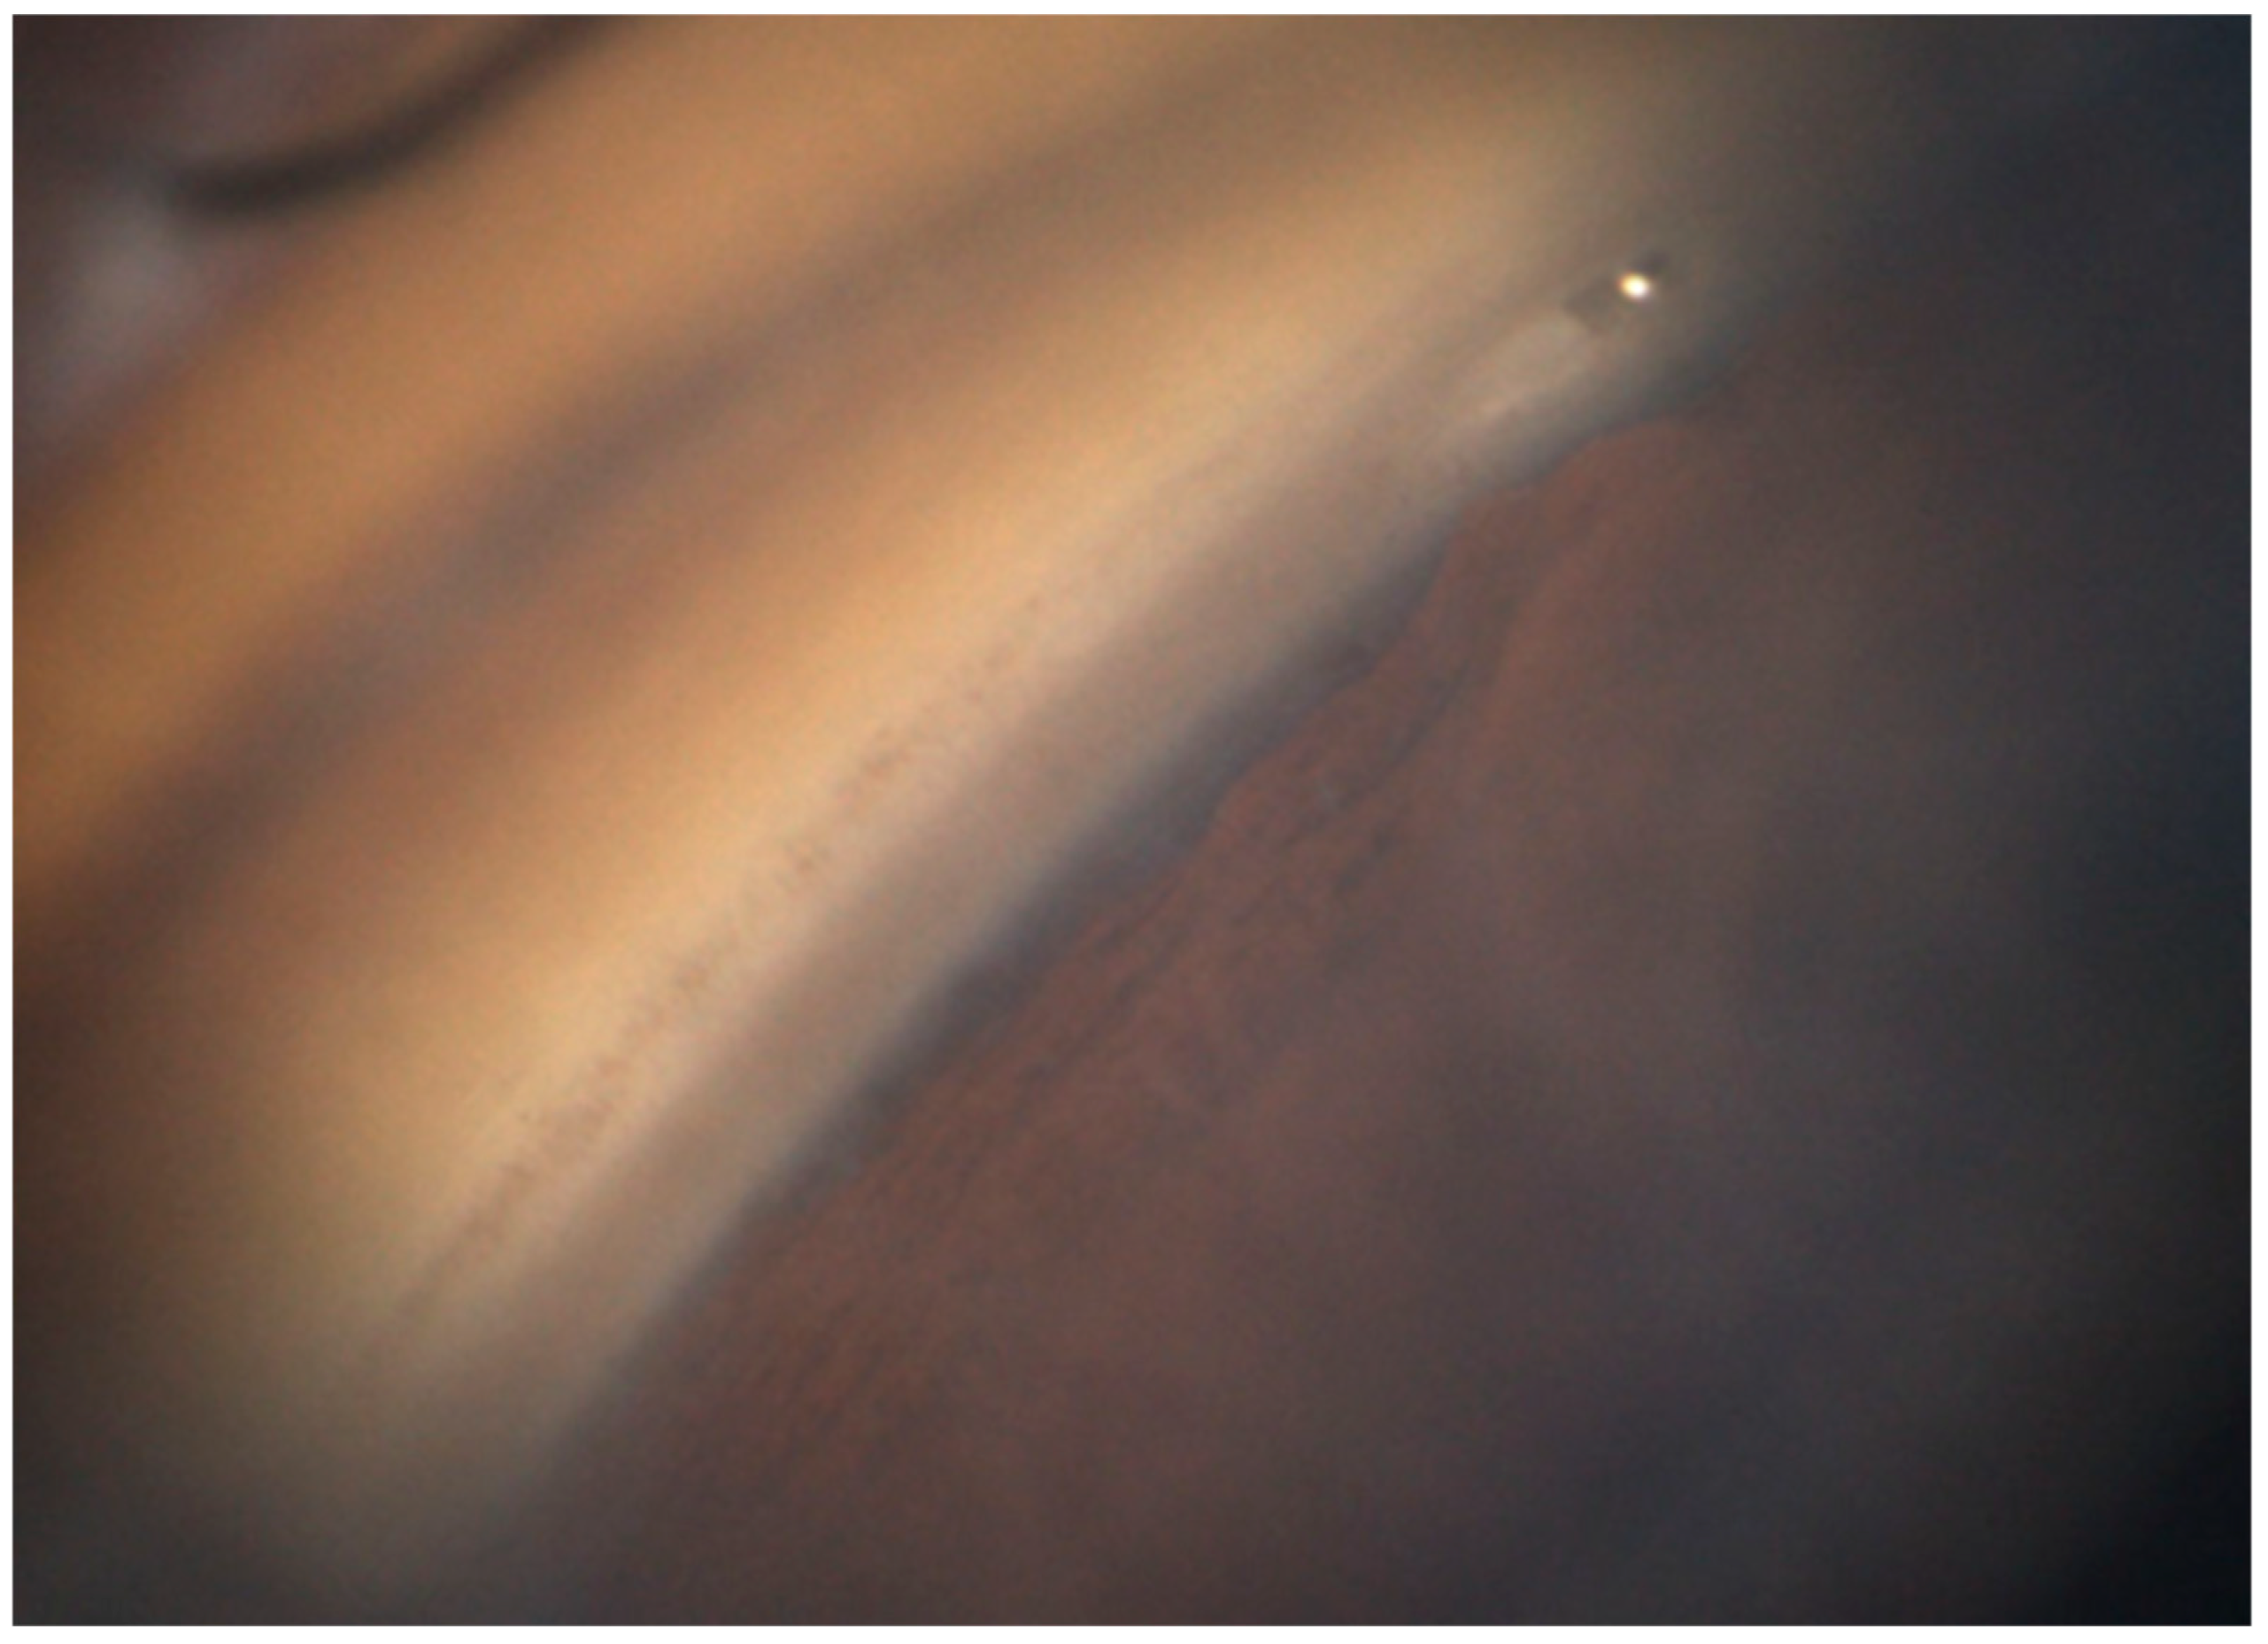

PAS was observed adjacent to seven stents in six eyes. The distribution of the stents based on insertion depth was six and one for Grades 1 and 2, respectively, with no significant differences (p = 0.180). TM clefts were identified around the implants in 10 stents across 10 eyes (Grade 1: 1; Grade 2: 9). The difference in cleft severity based on depth was significant (p < 0.001).

PAS was observed in seven stents across six eyes in the present study. While we anticipated a higher PAS rate with deeper insertions, no significant intergroup differences in insertion depth were observed. This suggests that postoperative inflammation and/or a pre-existing degree of angle opening have a greater influence. Future studies should investigate the relationship between angle width and PAS formation.

A TM cleft adjacent to the implanted iStent inject W was observed in 10 stents across 10 eyes. It was significantly more frequent for deep (Grade 2) insertions. The relatively large 360-μm flange of the iStent inject W likely results in greater compressive force on the surrounding TM with deeper placement, predisposing it to cleft formation. However, the frequency of this complication has not been confirmed because no direct comparison with iStent inject has been conducted. Therefore, further investigation is warranted.

Figure 2. Gonioscopic image showing peripheral anterior synechiae (PAS) around the iStent inject W. PAS is visible on the surface of the iStent inject W flange.

Figure 3. Gonioscopic image showing a trabecular meshwork cleft surrounding the iStent inject W. The device appears to have been over-inserted, as indicated by the trabecular meshwork clefts on both sides.